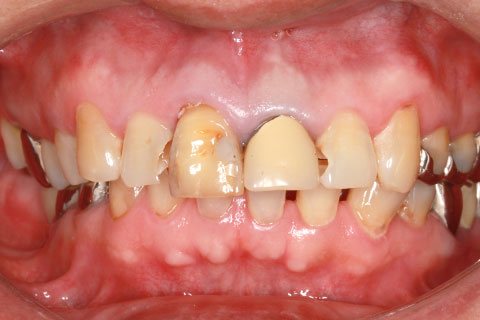

• メタルセラミック冠の症例1

治療前

治療後

年齢・性別

50歳男性

治療期間

1ヶ月

抜歯

なし

治療費

26.4万円

備考

前歯4本の古い被せをメタルセラミックにやりかえ。

治療内容

歯質を削除し、セラミック冠をセメント合着

施術の副作用(リスク)

知覚過敏